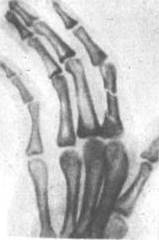

Перелом фаланг пальцев кисти чаще встречается у взрослых. По частоте стоит на I месте среди других переломов кисти. По статистике S. Bunnel (1956), составляет 50 % всех переломов кисти, 5,4 % — ко всем переломам скелета. Бывает изолированный перелом одной фаланги и множественный фаланг нескольких пальцев или нескольких фаланг одного пальца. По данным Б.К- Бабича (1960), Е.В. Усольцевой (1961), множественный перелом встречается в 20—29 % случаев по отношению ко всем переломам фаланг пальцев. Возникает в результате прямой травмы. Наиболее часто наблюдается перелом проксимальной и средней фаланг, реже — дистальных (16, с.78).

Рисунок 5 - Перелом основания средней фаланги 3 пальца кисти со смещением остеосинтез спицами.

Необходимое лечение переломов пальцев: Непременно следует добиться сопоставления отломков. Это необходимо для того, чтобы избежать утраты функции пальца. Если случился перелом без смещения, следует наложить на поврежденный палец ладонную гипсовую лонгету либо шину Белера. Делается это, как правило, примерно на один месяц. Если консервативным путем сопоставить отломки невозможно, тогда производят оперативное лечение. Специалисты обнажают отломки, а затем фиксируют одной или двумя спицами и костным штифтом, после этого накладывают гипсовую повязку сроком на один месяц. Порой используют скелетное вытяжение за ногтевую фалангу. Вскоре после того, как наложат гипс или произведут оперативное лечение, рекомендуется производить движения соседними пальцами (11, с.56).